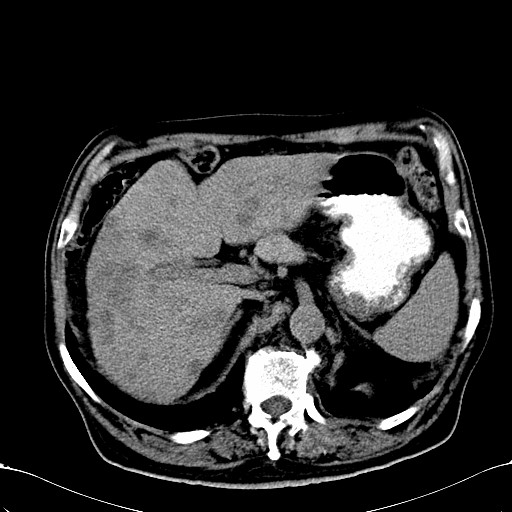

标题: CT28270:胰管扩张,肝多发占位

患者,男,75岁。

肝脏多方低密度结节,边缘模糊,考虑多发转移,胰管明显扩张,建议增强扫描钩突情况

肝脏多发低密度灶,胰头似呈低密度,胰管扩张,建议增强,

胰管显著扩张,但胆总管未见扩张征象,不太符合胰头占位!考虑慢性胰腺炎.胃窦占位并肝内转移可能!mrcp胃镜增强一起上!